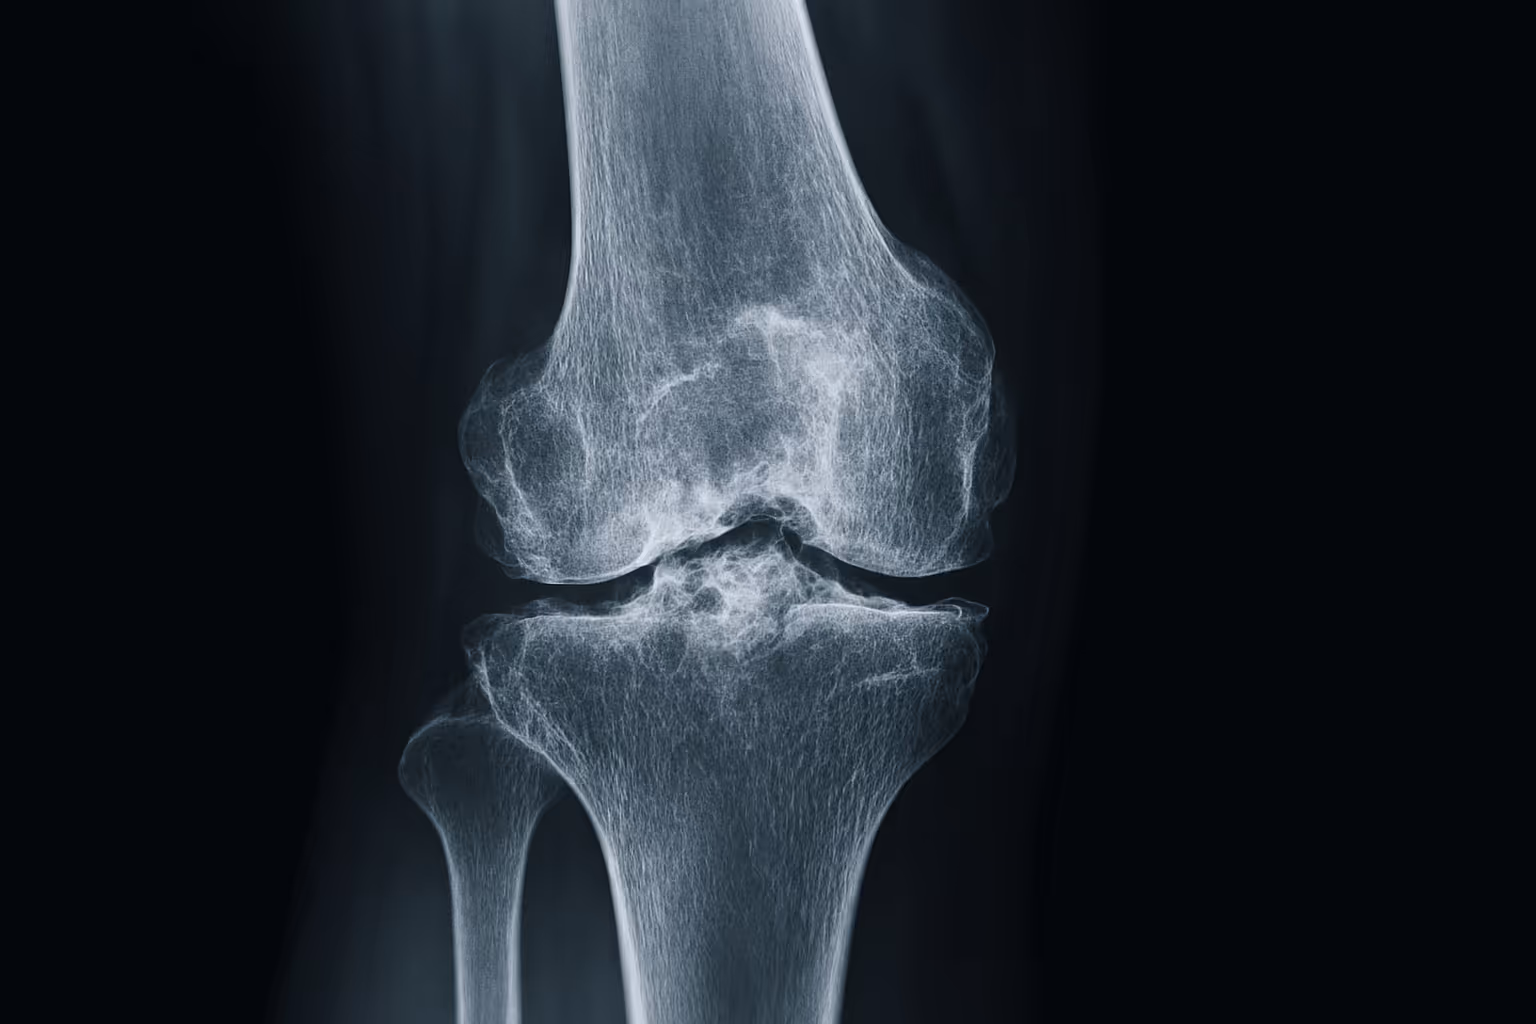

Radiology of Arthritis

Unlock the Secrets of Arthritis with Dr. Deltoff’s Radiology Insights